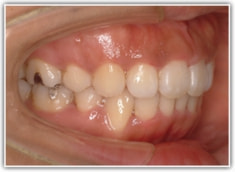

上顎前突ケース

治療法:表の矯正(T21ブラケット)

治療前